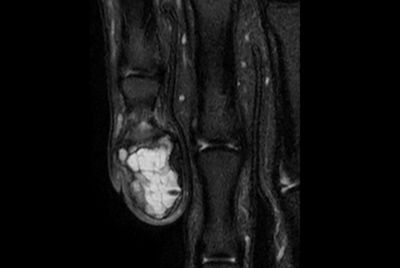

SmartSpeed Forefoot imaging